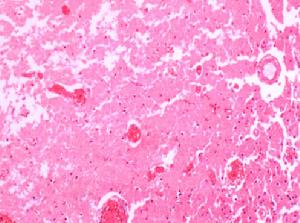

肺梗死是肺栓塞進一步的發展,在實際情況中肺動脈分支一旦血流阻斷,近毛細血管網處則因管壁缺氧滲透性增強,液體及紅細胞隨之滲出, 肺泡腔內滲出物增加,必然會使氣體交換受到影響,隨後肺梗死發生,這也是越近小動脈分支末梢堵塞越易發生梗死和梗死前必有出血的原因。手術或外傷後容易形成肺梗死,尤其是並發心血管疾病者,在肺淤血的基礎上更易形成肺梗死。